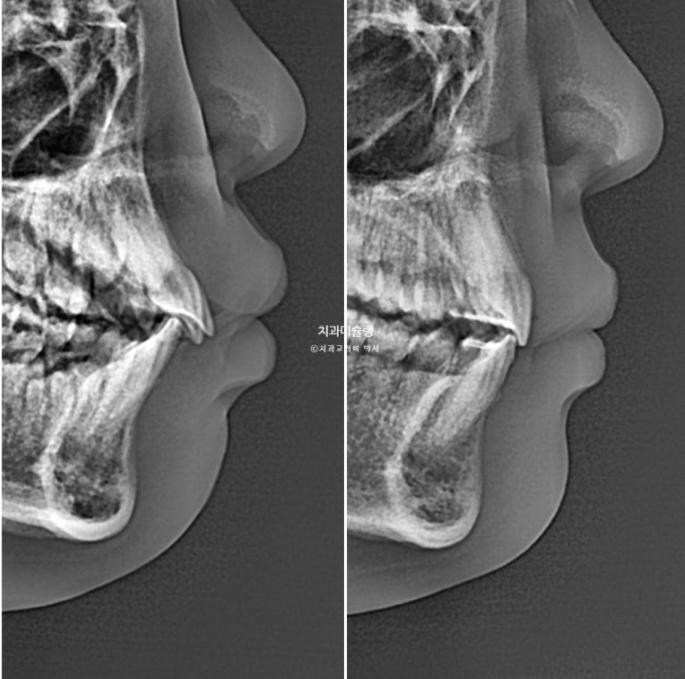

2년 전 교정치료를 위해 온 만 10세 어린이 입니다.

앞니가 하나 들려있고 깊게 물리는 과개교합이 있습니다.

중심선 불일치도 보입니다.

윗니 돌출이 측면에서 잘 보이네요.

23.11~25.08

윗니 아랫니 간격 차이가 줄며 입 다무는 게 편해집니다.

이 나이대 친구들이 앞니 돌출 때문에 입 벌리고 자는 습관이 생기면 구호흡에 의한 여러가지 부작용이 생깁니다.

얼굴이 길게 자라거나 입냄새가 나거나 충치가 잘생기거나 등

돌출입 성인되서 발치하고 교정해야겠다.

라는 생각보다는 미리미리 교정하는 게 좋습니다.